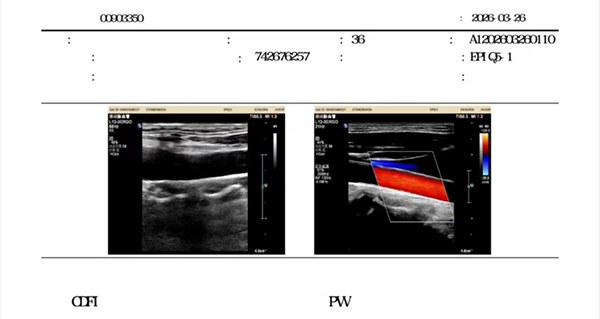

复查时:

04 3个月后复查:斑块完全消失!

坚持干预 3 个月后,体重仅仅下降1.5kg,但颈动脉B超显示7mm斑块彻底消失,查血显示丙氨酸氨基转移酶、天门冬氨酸转移酶、总胆固醇水平降至正常。